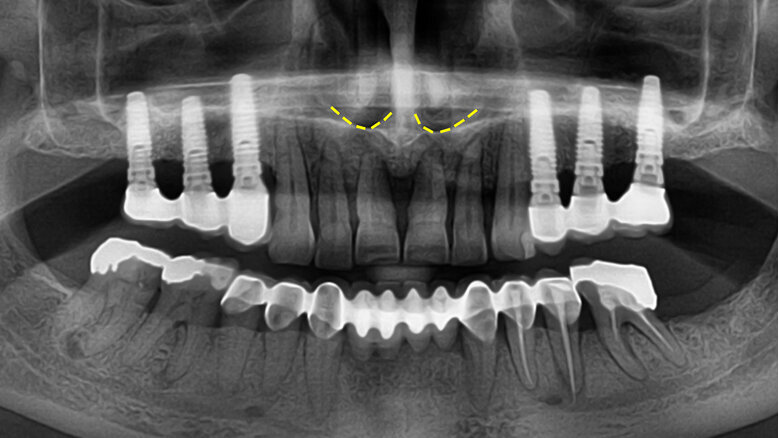

Frontální oblast maxily

Tato krajina je z implantologického hlediska stěžejní. Použitelnost augmentačních postupů (řízené regenerace kosti, intraorálních kostních štěpů, bone splittingu) určených ke zvětšení tloušťky kosti je omezená. Zvýšit nízkou interantrální kost nazálním liftem nebo intraorálním kostním štěpem je v prvním případě nejisté a ve druhém případě značně obtížné. Autoři nemají v této oblasti dobré zkušenosti s krátkými implantáty. Preferují fixtury dlouhé nejméně 12 mm, v krajním případě desetimilimetrové. Výhodnější jsou fixtury středního průměru než tenké.

Souhrn: Rozměry kosti ve frontální oblasti maxily jsou pro implantaci bezzubých pacientů limitující. V případě ne plně stabilizované parodontitidy je třeba ukončit parodontologickou terapii a extrahovat zuby tak, aby alveolární výběžek po zhojení extrakčních ran dosahoval výšky minimálně 12 mm (v nouzi 10 mm) a tloušťky nejméně 5–6 mm (obr. 4). Toto explicitní numerické vyjádření je však jen orientační, modifikovatelné konkrétními podmínkami, zejména žvýkací silou a stavem protilehlého zubního oblouku.

3. U kandidátů implantační terapie s ne plně stabilizovanou parodontitidou existuje okamžik, kdy je vhodnější parodontologickou terapii ukončit a přirozené zuby odstranit v zájmu zachování alveolární kosti.

4. Okamžik ukončení parodontologické léčby je ovlivněn především rozměry alveolárního výběžku ve frontální krajině horní čelisti. Zuby by měly být extrahovány včas, aby se po zhojení extrakčních ran alveolární výběžek nesnížil pod 12 mm (v krajním případě pod 10 mm) a neztenčil pod 5–6 mm.